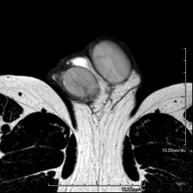

- Knee MRI

Examination to study joint injuries, such as meniscal tears and cruciate ligament tears (only detectable through this test), chondropathy or cartilage wear, and a multitude of other disorders resulting from sports activities and degenerative changes (osteoarthritis). It lasts approximately 18 minutes. It is a radiation-free procedure.